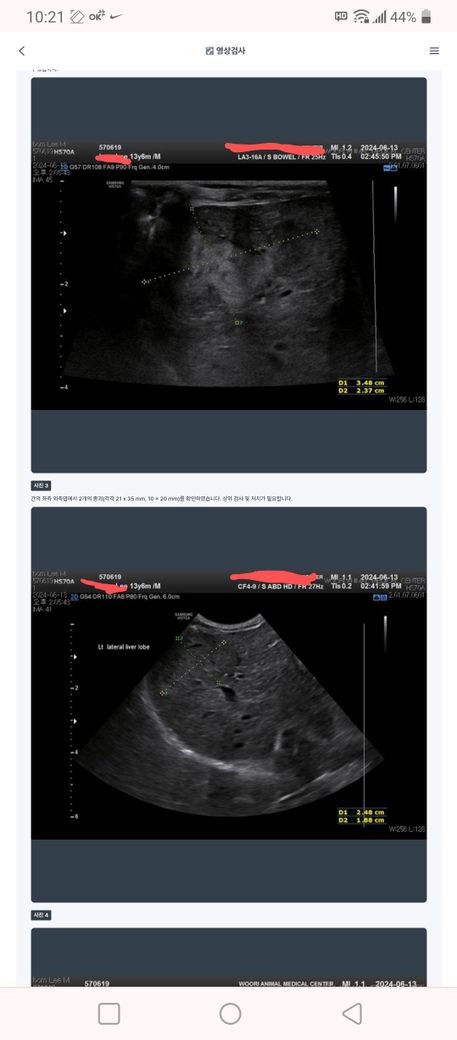

초음파상 간종괴 판정 받았습니다.

간종괴 3.5cm 와 1cm 2개 발견됬고.

Alt 200 입니다.

백혈구 조금 낮고.

나머지 혈액검사는 정상 입니다.